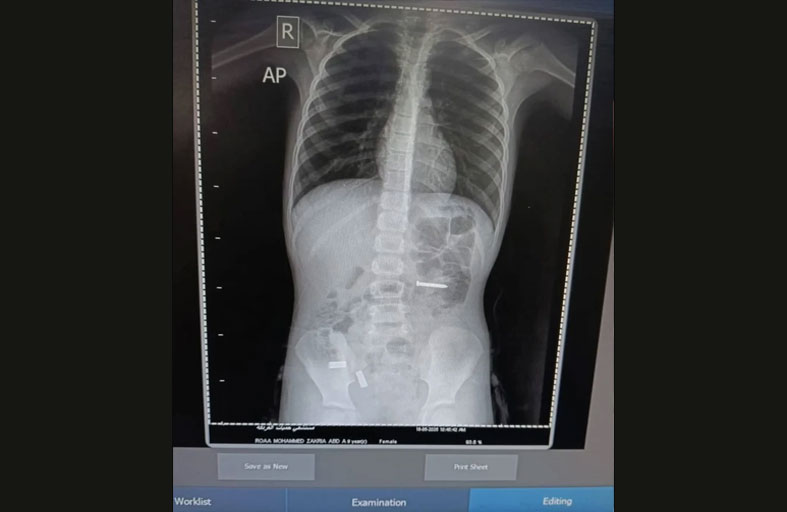

في حادثة طبية غير معتادة، استقبلت مستشفى حميات الغردقة في مصر، حالة طارئة لطفلة تبلغ من العمر 9 سنوات، تعاني من آلام حادة في المعدة، فيما كشفت الفحوصات الأولية عن مفاجأة، حول وجود جسم معدني غريب داخل الأمعاء. وبحسب تقارير محلية، خضعت الطفلة لأشعة دقيقة، أظهرت بوضوح وجود جسم صلب في المسار الهضمي، دفعت الفريق الطبي لتجهيز الطفلة فوراً لدخول غرفة العمليات. وخلال ساعة واحدة فقط، تمكّن الفريق من استخراج المسمار المعدني، والذي بلغ طوله 3 سنتيمترات، وانتهت العملية بمنتهى الدقة، مع الحرص الشديد على تجنب أي ضرر أو مضاعفات للجهاز الهضمي. وبعد انتهاء العملية، خرجت الطفلة من غرفة العمليات إلى قسم الملاحظة بحالة مستقرة، حيث وُضعت تحت المراقبة الطبية الدقيقة للتأكد من سلامة وظائف الجهاز الهضمي واستقرار وضعها الصحي.